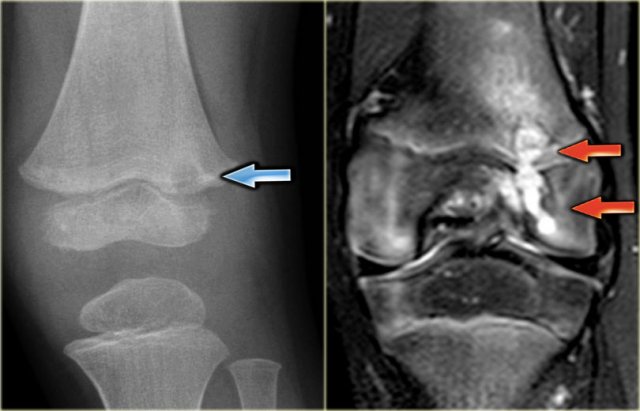

Here images of a 30-year-old male.

There is a wel-defined lytic lesion of the olecranon with several ridges and a pathologic fracture.

The differential diagnosis includes giant cell tumor and ABC.

The T2WI+FS shows fluid-levels due to sedimentation making ABC the most likely diagnosis.

Biopsy however revealed Brown tumor.